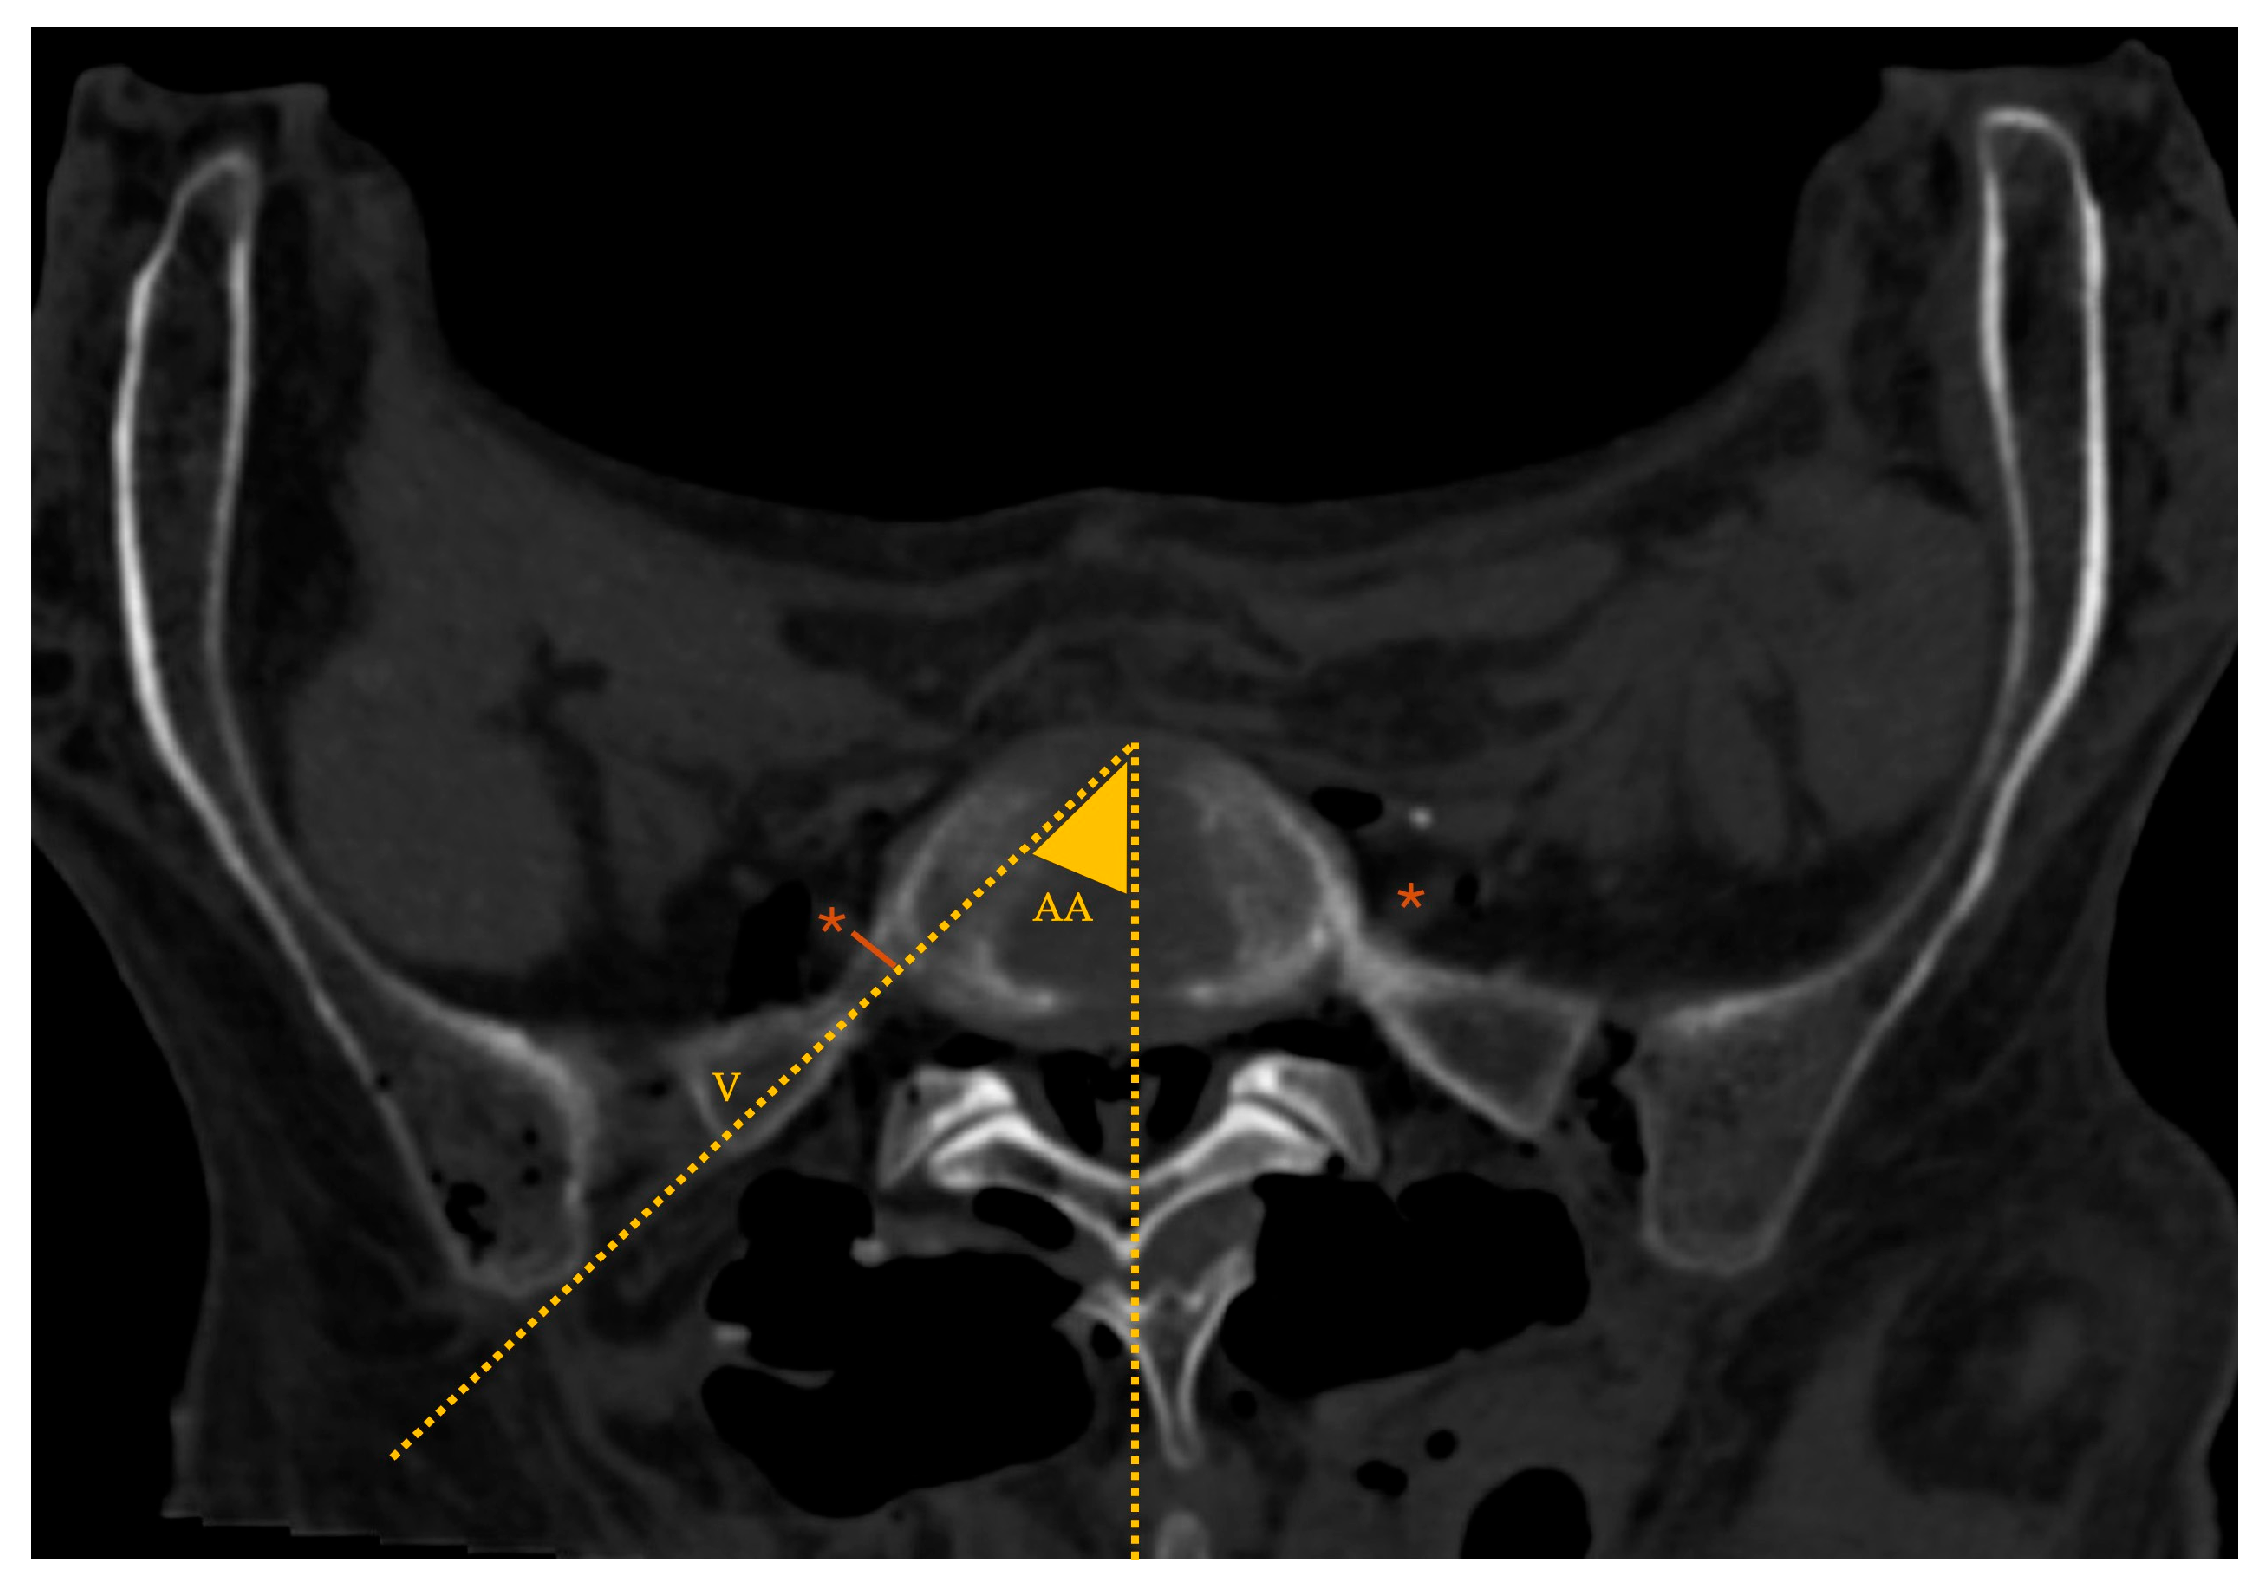

• MaxTP-sacrum and minTP-sacrum: maximum and minimum distance from the inferior border of the L5 TP to the superior border of the sacral ala, respectively, (coronal plane intersecting the L5 TP center; Figure 3)

• Approach angle (AA): angle between the midline and the vector (V) tangential to the iliac crest that crosses the most anterior point of the L5-S1 disc space (axial plane at IVD space; Figure 5)

• MinL5-V: minimum distance from the ventral ramus of the L5 spinal nerve to V (axial plane; Figure 5)

The maxTP-sacrum distance (Figure 3) was 11.1(4.0)mm, consistently located in the second quarter of the L5 TP (from its base). The mean minTP-sacrum distance (Figure 3) was 5.6±2.9mm, always near the L5 TP tip. No statistically significant differences were observed between nondysmorphic and dysmorphic upper sacral morphology (p=0.662 and p=0.498, respectively).

The mean AA (Figure 5) was 35.2±5.0°. An EF vector (V) tangential to the iliac crest that crosses the most anterior point of the L5-S1 disc space defined a workable corridor to the L5-S1 disc in 75% of the cases (18/24 sides). These cases had significantly greater AA (29.9±3° vs 37.2±4°; p=0.02) and despite not statistically significant, larger TP to sacrum distances, greater EF-areas, and increased minL5-V values were found. However, in 44% (8/18) of cases with a workable corridor on CT based on AA the distance to the ventral ramus of the L5 spinal nerve was inferior to 5mm.

The median minL5-V distance was 5.0(7.1) mm, with no statistically significant gender (p=0.788) or sacral morphology (p=0.429) variation. This parameter was zero in 8 out of 24 cases (33%), meaning direct overlap between the vector V and the ventral ramus of the L5 spinal nerve.

Figure 5. Lumbar spine CT – axial plane; *: ventral ramus of the L5 spinal nerve; dotted yellow lines: marking of the approach angle (AA; angle between the midline and the vector (V) tangential to the iliac crest that crosses the most anterior point of the L5-S1 disc space; solid orange line: minL5-V (minimum distance from the ventral ramus of the L5 spinal nerve to vector line).